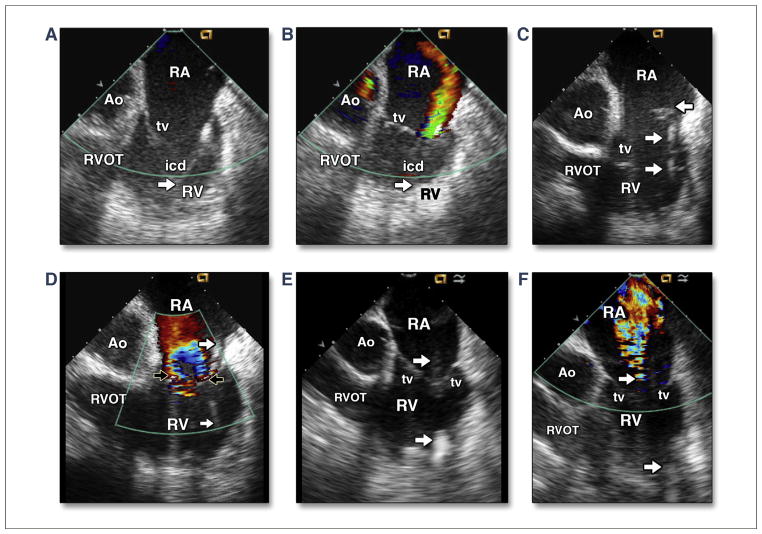

FIGURE 1. Intracardiac Echocardiographic Images of Intracardiac Device Lead and Tricuspid Regurgitant Severity With Different Etiologies.

Intracardiac echocardiographic imaging with the transducer placed in the right atrium in 3 patients. The first patient had severe left ventricular (LV) dysfunction (left ventricular ejection fraction [LVEF] = 20%), normal right ventricular (RV) size, and pulmonary artery systolic pressure (PASP) estimated at 55 mm Hg, an implantable cardioverter defibrillator (ICD) lead (arrow) placed at the RV anterolateral wall with impingement of the posterior leaflet (A), and moderately eccentric tricuspid regurgitation (TR) with color Doppler imaging (CDI) (B). The second patient had moderate LV dysfunction (LVEF = 35%); enlarged RV and tricuspid annulus; PASP of 51 mm Hg; an ICD lead (rightward arrows) placed at the RV apex; multiple small thrombi (leftward arrow) attached at the lead (C); and severely centralized TR with CDI, which shows that the lead (arrows) is slightly impinging the posterior leaflet (D). The third patient had arrhythmogenic RV cardiomyopathy, enlarged RV and tricuspid annulus, PASP of 33 mm Hg, LVEF = 30%, a centralized location of ICD lead (arrows) placed at the RV apex (E), and moderately to severely centralized TR with CDI (F). Ao = aortic root; RA = right atrium; RVOT = RV outflow tract; tv = tricuspid valve.

With routine clinical application of intracardiac echocardiography (ICE), RV anatomy and function (3) and many of the valvular etiologies of TR can be identified and assessed in real time. Real-time ICE imaging has superior capability to image the course of the device lead from the right atrium to the RV. The device-lead location and route passing through the annulus can be imaged. TR induced by intracardiac device-lead impingement and its severity can be accurately assessed (Figures 1A and 1B). However, independent of lead position, moderate-to-severe and mainly centralized TR can be commonly detected in an enlarged and dysfunctional RV, secondary to left ventricular (LV) dysfunction/heart failure (Figures 1C and 1D) or due to arrhythmogenic RV cardiomyopathy (Figures 1E and 1F) with recurrent ventricular tachyarrhythmia. It is strange that this paper found no difference in TR severity in ICD versus pacemaker lead implantation. Our clinical observations with ICE imaging may indicate that ICD leads with more thickness and rigidity have higher events of TR than standard pacing leads, as others have reported previously (4).